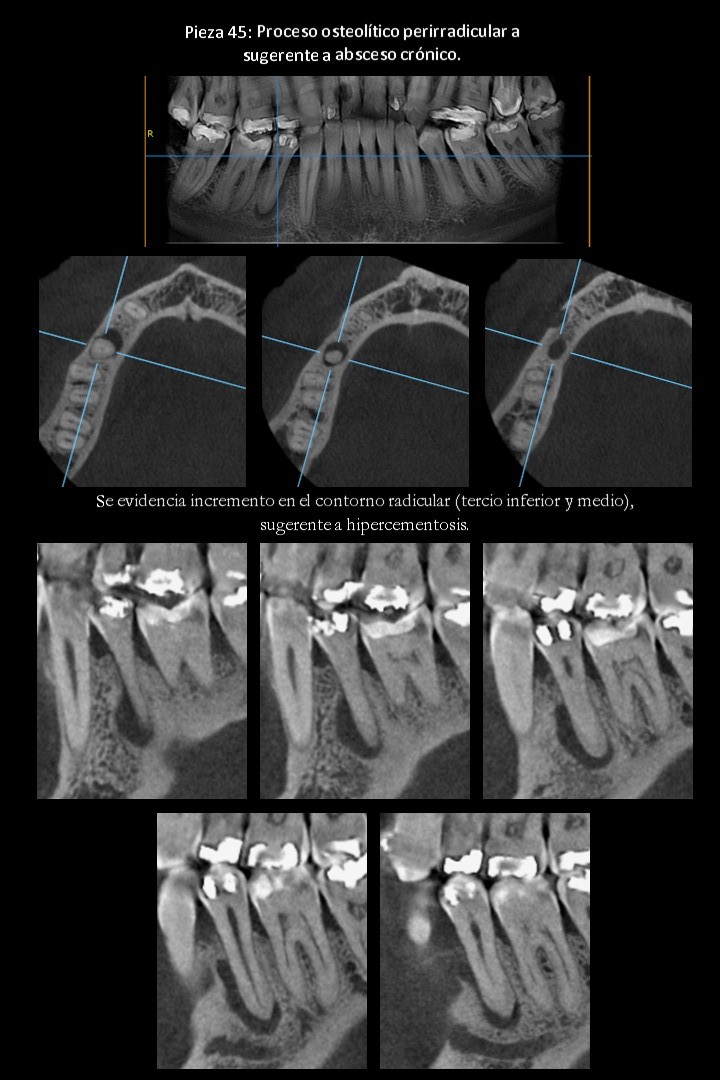

CASO 1 (absceso crónico).

A la evaluación de la tomografía computarizada volumétrica (TCCB), para el maxilar superior e inferior (evaluación general), se observa:

Evaluación de las piezas dentales.